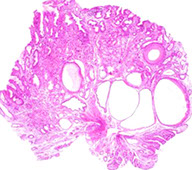

Adenocarcinoma

Adenocarcinoma (AC)

MCC stomach cancer (90-95%), M>F, higher risk in Eastern countries, South America, AMAG also puts at risk; is occurring more in gastric cardia

- Can be divided into intestinal (bulky) and diffuse (more often have signet ring cells) types

Intestinal type AC assoc c H pylori infx

-- Lauren classification found intestinal type-tumors have better survival than diffuse type

Hereditary diffuse gastric carcinoma assoc c mutation in E-cadherin or alteration of its gene expression

- has AD pattern of inheritance

Early aggressive local spread and lymph node/ liver mets

- asymptomatic until late; mets usually found at dx

Assoc w/ nitrosamines (smoked foods), achlorhydria, chronic gastritis (H pylori), type A blood

- gastric adenomas and dysplasia are precursors

Signet ring cells and acanthosis nigricans common features.

Linitis plastica ("leather bottle") may occur when diffusely infiltrative

Tumor may also be: ulcerating, polypoid, or superficial spreading

Virchow node: mets to L. supraclavicular node

Krukenberg's tumor: bilateral mets to ovaries. Abundant mucus, Signet ring cells

Sister Mary Joseph nodule: subcutaneous periumbilical mets

Irish node - enlarged left axillary lymph node

Leser-Trelat syndrome: sudden dermatologic onset of seborrheic keratosis (look for underlying gastric malignancy)

Micro: intestinal type tumors are large masses that form c intestinal metaplasia in background

- diffuse type seem to arise de novo in normal mucosa background, can be sneaky and have signet rings and look like macrophages from lower power

- may appear hepatoid (poor px; +SALL4), clear cell, squamoid, micropapillary

- lymphoepithelial-like AC is lacy and can be EBV+

IHC: (+) HER2 regularly suggested (from ToGA trial; HER2 IHC is superior to FISH), CDX2, CK7, CK20 (while keratins can be helpful, should not be used on all ulcers bc can highlight scurry lookin single cell pattern in regenerative tissue); PAS/AB reveals abnormally colored cells and has strange effect on mucin;

- negative CD44, EBV, E-cadherin (in hereditary AC)

Like breast cancers, ~20% of gastric cancers and 30% of gastroesophageal junction cancers overexpress HER2

- unlike breast cancer Her2 overexpression by either FISH or IHC is evidence of likely response

Labs: inc CEA in 45-50%; CA19-9 in 20%

- may consider HER2 by FISH if IHC is equivocal

Genes: ~1/2 sporadic diffuse are hereditary, assoc c CDH1 gene (encodes E-cadherin); has 7/10 penetrance; esp get signet ring AC and also assoc c lobular ca of the breast

- prophylactic gastrectomy may be offered to CDH1 gene carriers; CDH1 mutations assoc c gastric signet ring ca and lobular carcinoma of the breast

- sporadic intestinal type assoc c Wnt pathway mutations (such ass loss-of-function of APC tumor suppressor gene and gain-of-function of B-catenin

DDx: chemical gastropathy, crushed oxyntic mucosa

Tx: Distal 1/3: subtotal gastrectomy

- proximal 2/3 or infiltrative lesions: Total gastrectomy w/ adjuvant chemo and rads

- trastuzumab in HER2+ cases

Px: depth of invasion and extent of nodal and distant mets are most impartant px factors

- 1/2 of pts die of dz; AC found outside cardia has better px vs gastric cardia AC

- stage assoc c survival (Lauren classification)

AJCC staging Gastric cancer